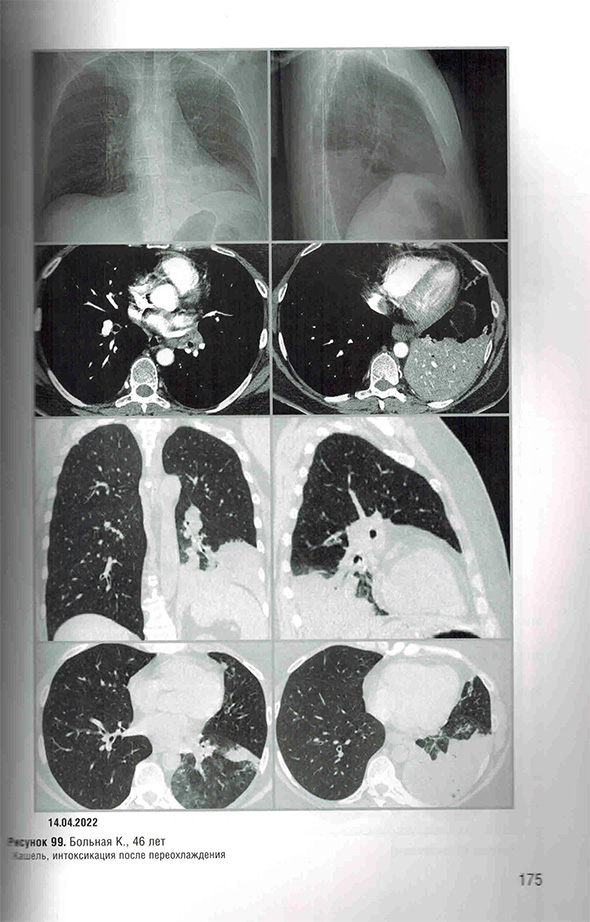

Протокол «ФБЛ (постковидные изменения)»